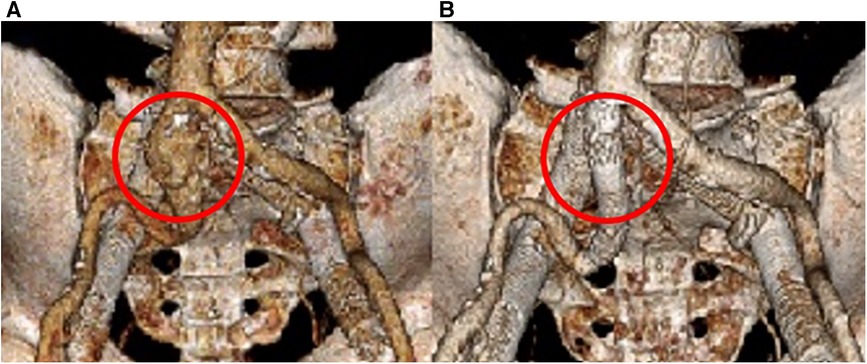

Follow-up imaging 6 months later demonstrated an increase in the size of the right CIA aneurysm (Figures 3B,C). Therefore, the patient was taken for a staged intervention of the aneurysm with the placement of covered iliac stents using a 13.5 mm Fluency self-expanding (Bard Peripheral Vascular, Tempe, AZ, USA) and 10 mm iCast stents (Atrium, Hudson, NH, USA) in overlapping fashion from the ostium of the right CIA to the bifurcation of the internal–external iliac arteries. These stents were chosen due to sizing availability at the time over the traditional EVAR limb. The Fluency stent was initially used as it would result in adequate coverage without an obvious endothelial leak. Once the covered stent was placed in the proximal CIA, we proceeded with placing a 1:1-sized iCAST stent to ensure appropriate coverage of the aneurysmal segment. Follow-up CTA demonstrated a regression and thrombosis of the aneurysm and patent, well-aligned venous stents, Figure 3D. The near resorption of the native aneurysm sac can be discerned from Figures 4A,B. Because of the placement of the stents and resumption of anticoagulation, the patient has had no further reoccurrences of DVTs or other related symptoms.

Figure 4. 3D reconstruction of the arterial system. (A) Initial imaging revealing the right CIA aneurysm. (B) 18 months post-covered stenting shows a complete resolution of the aneurysm.